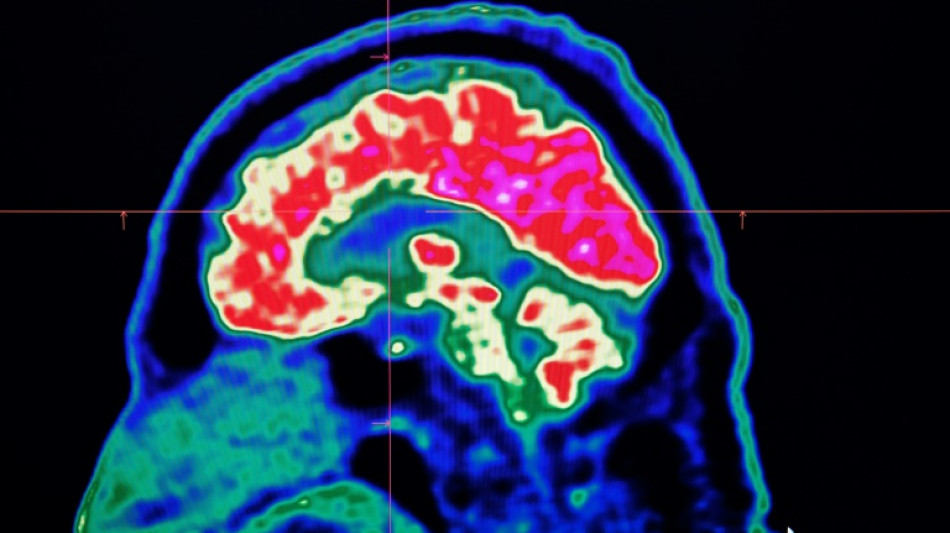

Surging nervous system disorders now top cause of illness: study

Conditions affecting the nervous system -- such as strokes, migraines and dementia -- have surged past heart disease to become the leading cause of ill health worldwide, a major new analysis said on Friday.

More than 3.4 billion people -- 43 percent of the global population -- experienced a neurological condition in 2021, far more than had previously been thought, the analysis found.

The researchers looked at how 37 different neurological conditions affected ill health, disability and premature death across 204 countries and territories from 1990 to 2021.

More than 443 million years of healthy life were lost to nervous system disorders globally in 2021, an 18-percent increase from 1990, the study found.

Stroke, which was previously counted as a heart disease, was by far the worst neurological condition analysed, accounting for 160 million years of healthy life lost.

It was followed by a form of brain damage called neonatal encephalopathy, migraine, dementia including Alzheimer's disease, nerve damage from diabetes, meningitis and epilepsy.